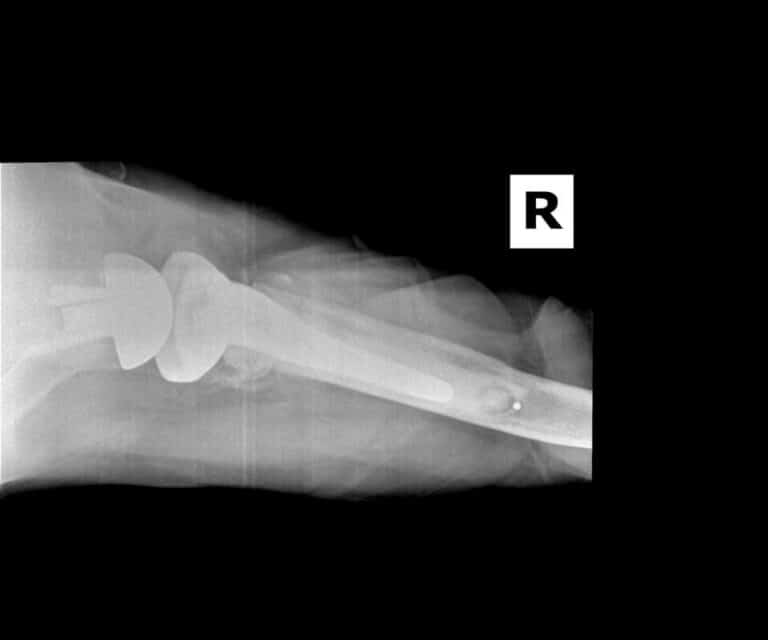

American Shoulder and Elbow Surgeons > Stryker/Wright/Tornier, Aequalis

Stryker/Wright/Tornier, Aequalis